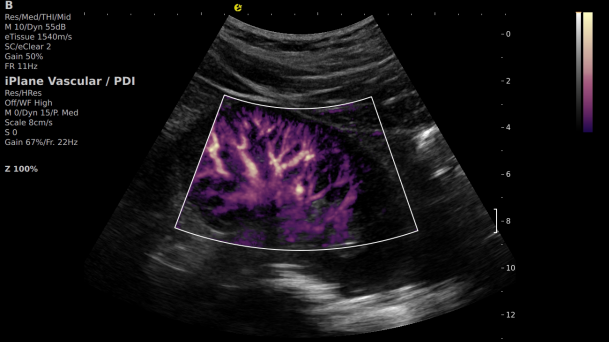

在肾移植领域,医生最怕的不是手术刀下的惊心动魄,而是那些手术后肉眼看不见的危机——急性排斥反应导致的血小板聚集形成的微血栓、毛细血管网损伤等...这些“隐形杀手”曾让无数移植肾在悄无声息中衰竭。而利来国国际网站医疗(ESI)的iPlane Vascular平面波超微细血流显像技术,正是为破解这一难题而生。

这项革命性技术通过三大创新实现质的飞跃:

1) 基于OmniSound?平面波超快速平台,超声信号采集帧频提高了200倍(25000Hz)。

2) 可检测20-50μm级细小血管低速血流信号,能看清头发丝1/2粗细的微血管;

3) 通过血管指数(VI)定量评估局部血管密度,以定量化数据实时监测血流灌注情况,预判肾功能恢复情况;

超微视血流显像显示肾脏五级血管

从术前评估到术中到术后,再到终身监护,当20-50μm级的超微血流信号在屏幕上跳动,我们看到的不仅是技术的精进,更是生命的律动。iPlane Vascular正在重新定义肾移植监护的标准——让医生拥有了"显微视力",让每一个微小血管的异常都无所遁形,让每一次免疫排斥的萌芽都被及时扼制。